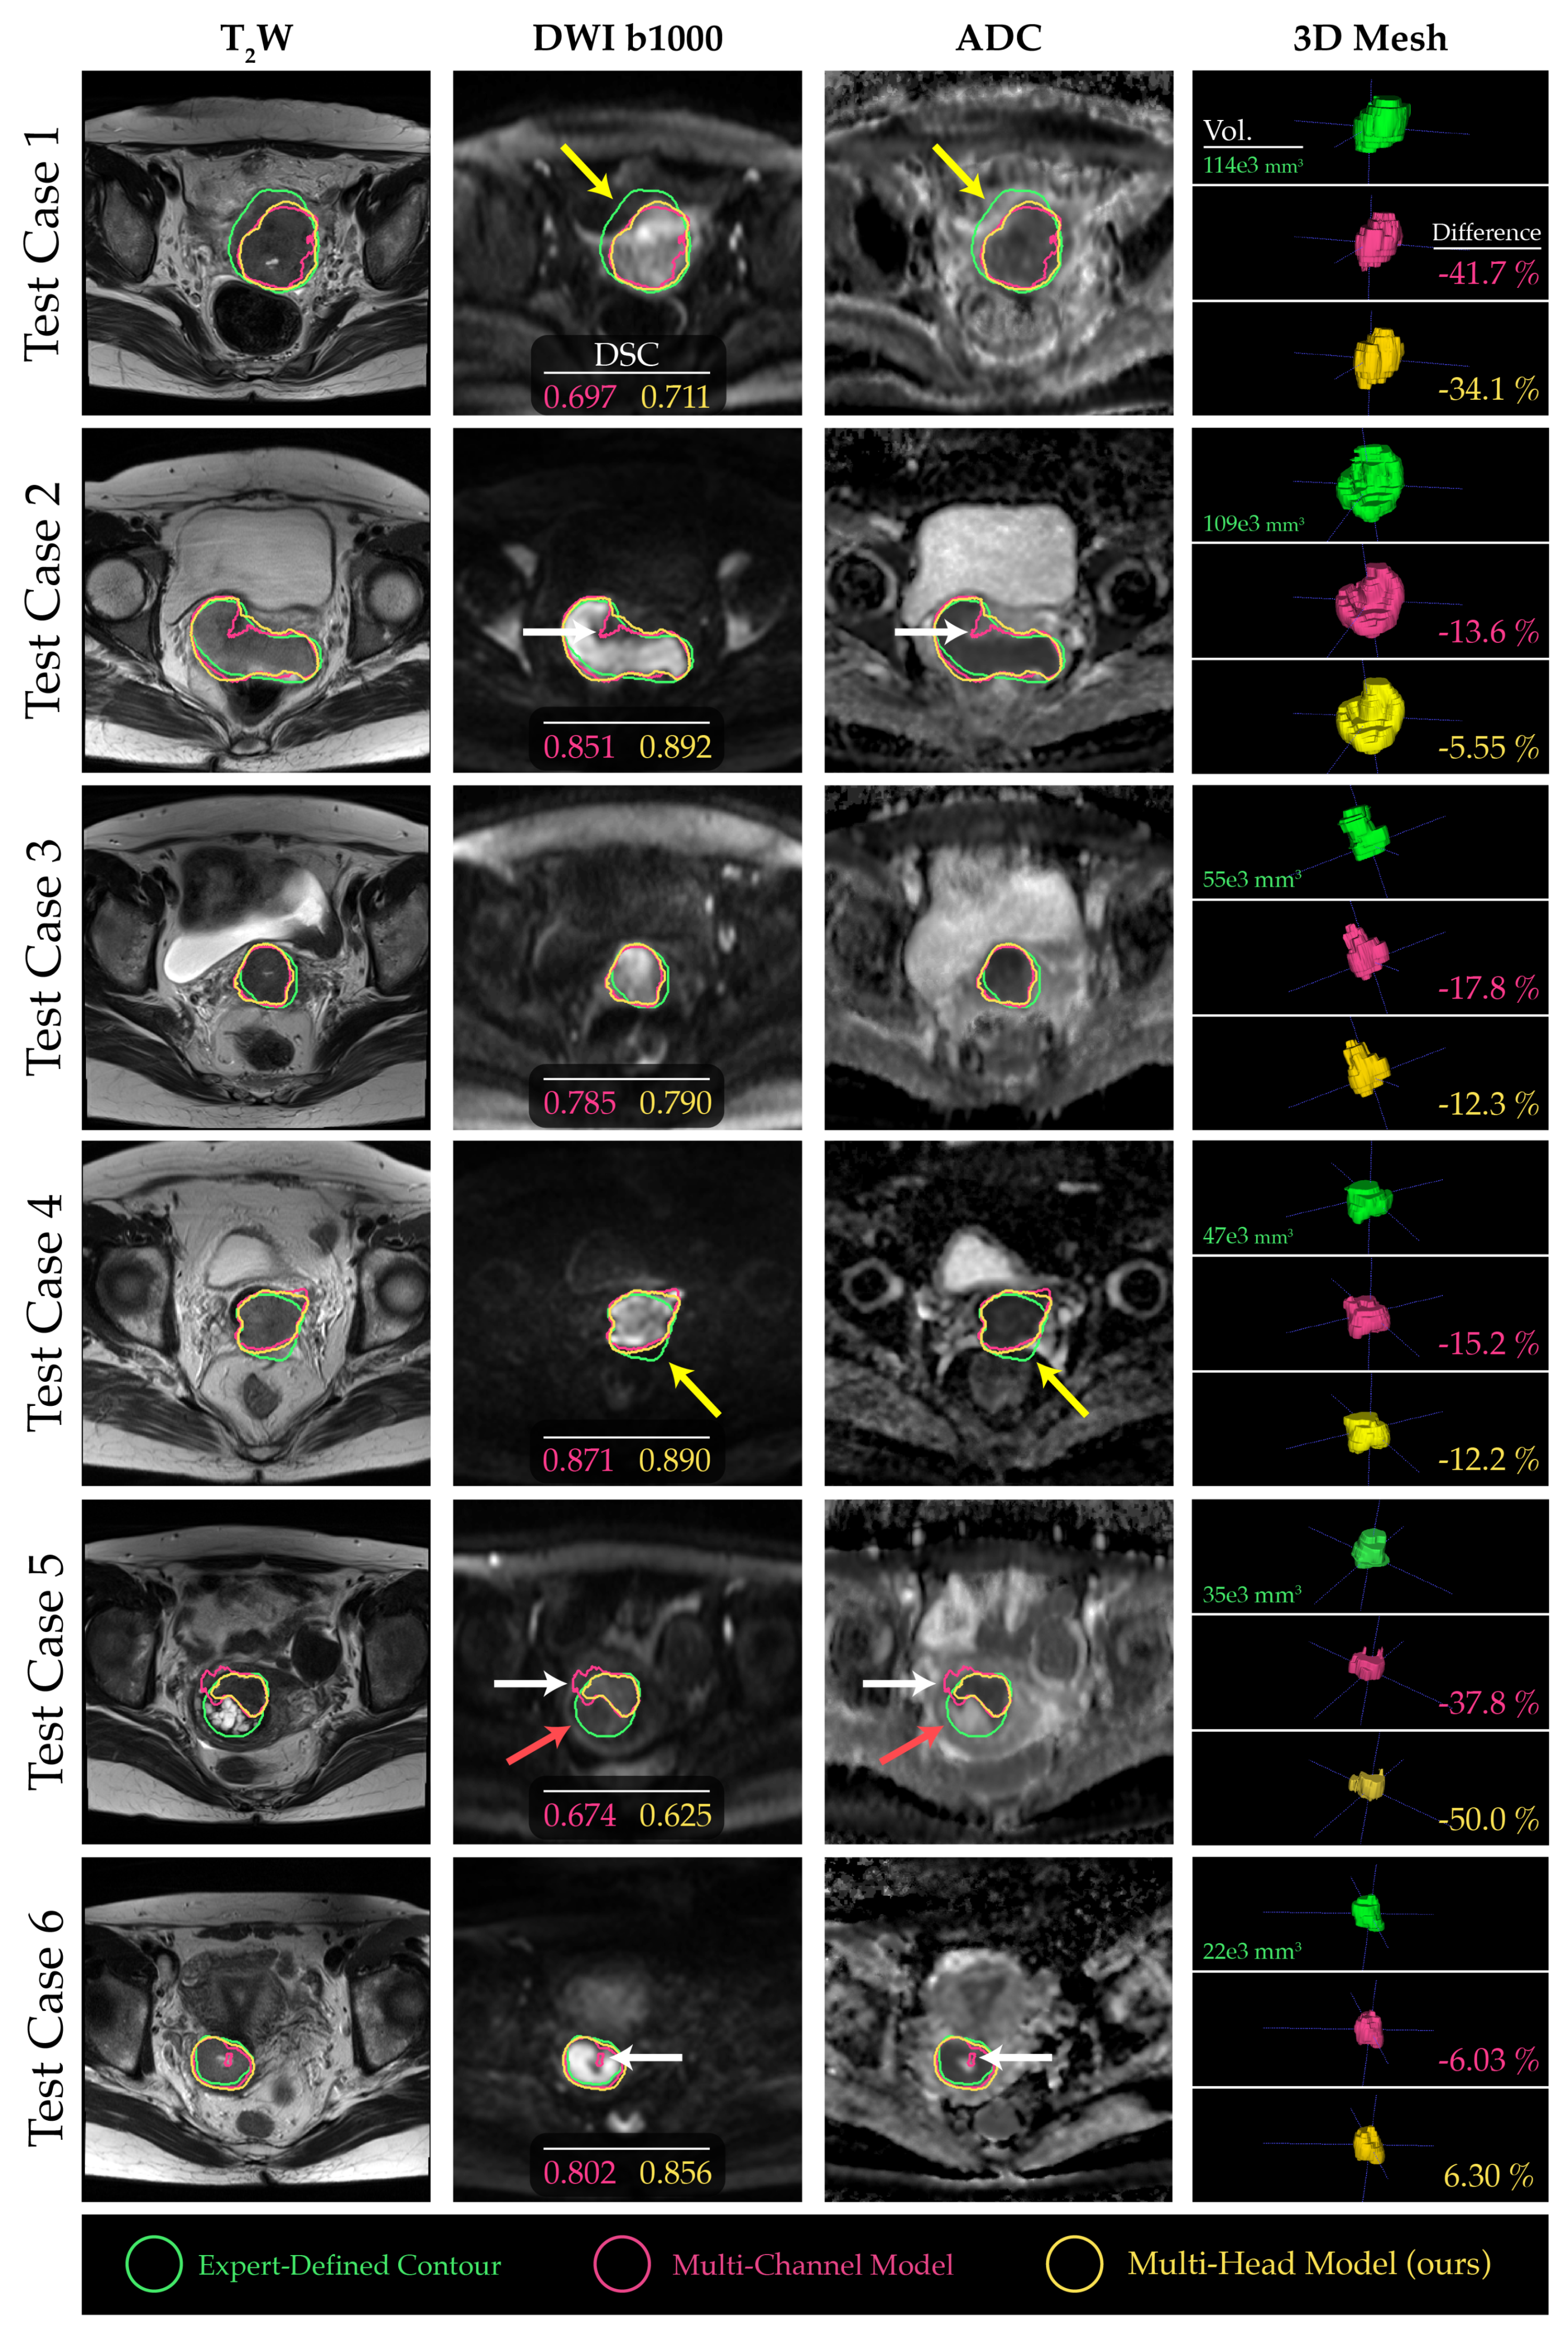

3. Results